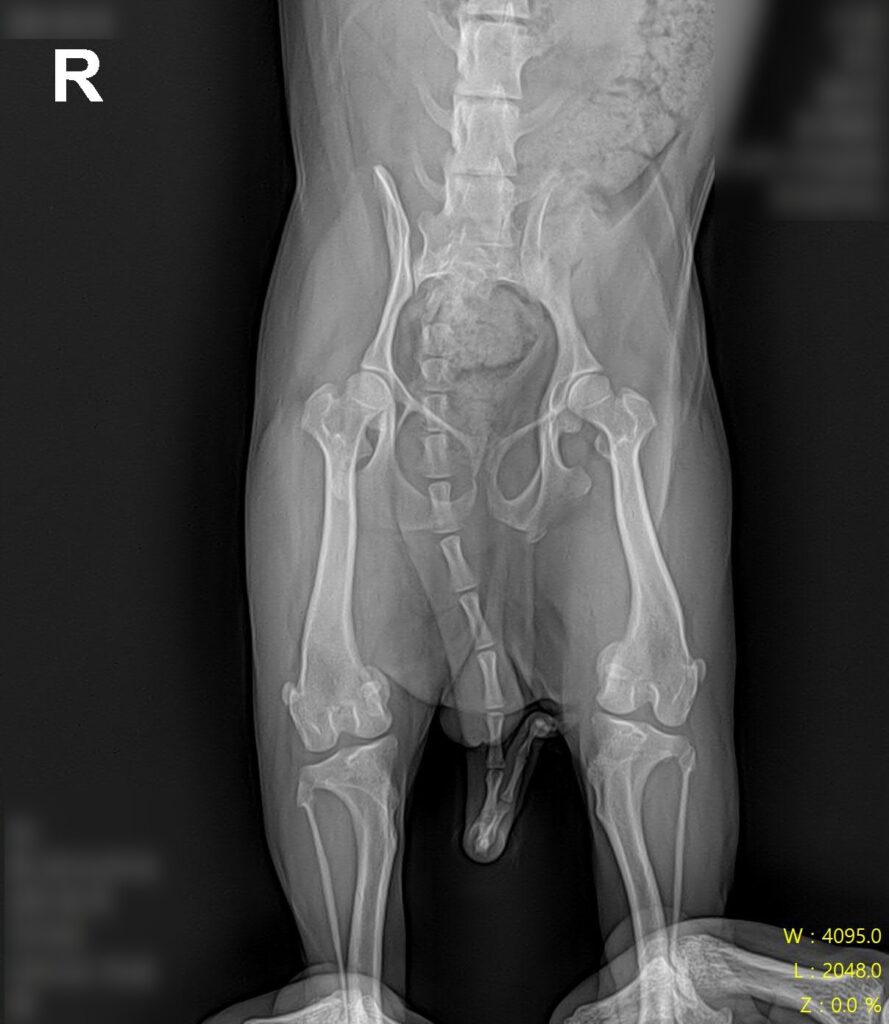

마취 전 방사선 검사 / 출처: 라온동물메디컬센터

정형학적 검사와 방사선 영상 검사를 진행한 결과, 슬개골탈구 4기(말기, terminal) 소견이 확인되었습니다. 슬개골이 완전히 고정 탈구된 상태였고, 활차구의 심각한 평탄화와 경골 조면의 내측 편위, 다리뼈의 비틀림이 동반되어 있었습니다.

2년 전 3기 진단 당시와 비교하면 그 사이 조용히, 그러나 빠르게 진행된 것이었어요. 보행이 크게 불편해 보이지 않았던 이유는 강아지가 변형된 뼈 구조에 스스로 적응하며 걷고 있었기 때문입니다.